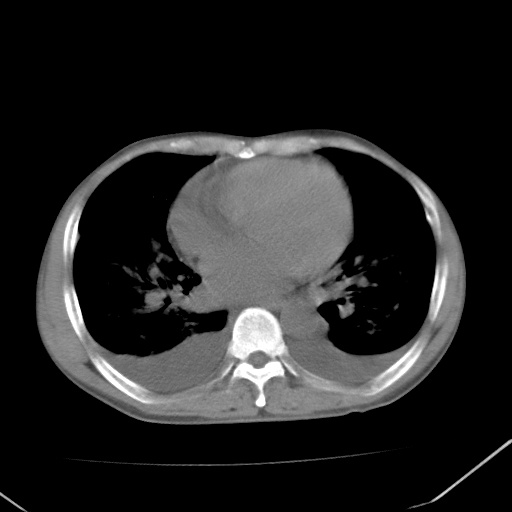

双肺野对称性磨玻璃影,分布于内中带,双侧胸水,患者有咯血。

双肺野广泛对称性磨玻璃影、实变影,以肺门为中心,主要分布于内中带,符合典型肺泡性肺水肿;伴双侧胸腔少量游离积液。结合患者既往病史且咯血就诊,支持多因素(尿毒症等)所致之肺水肿、肺出血、胸水;影像表现暂不考虑心源性水肿,且症状也不太符。需密切随诊结合临床治疗等进一步明确。

心影增大密度略低,双肺磨玻璃样高密度影及双侧胸腔积液,考虑心功能不全继发双肺肺水肿及双侧胸腔积液。心影密度略低,考虑贫血所致。

结合病史考虑双肺泡积血,双侧胸腔少量积液;肺水肿待排(肺水肿症状重)。